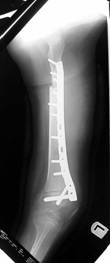

Left tibia lengthening with fixator in place

Follow Up

Lengthening tibia on Xrays in progress

Lengthening proceeding